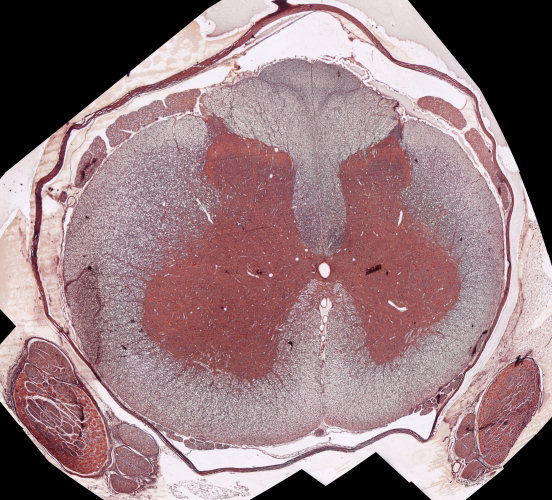

Grysstof / Grey matter

Witstof / White matter

Spinaalganglion / Spinal ganglion

Sentrale kanaal / Central canal